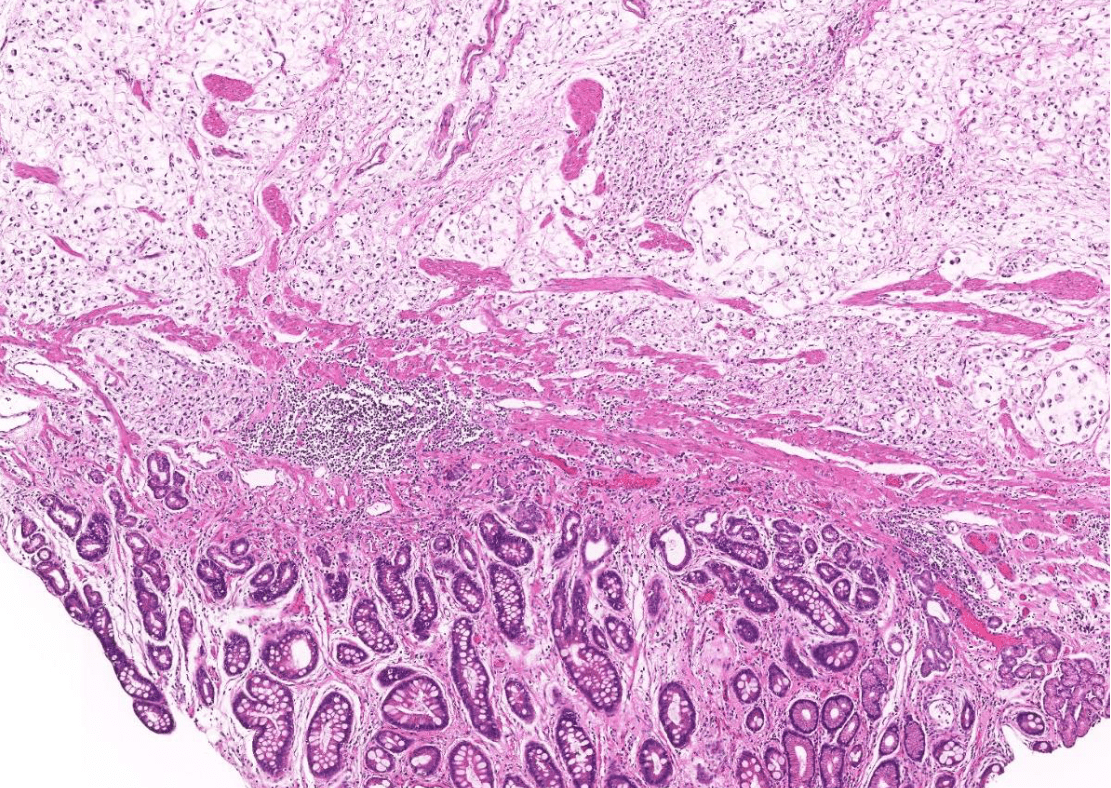

colon cancer